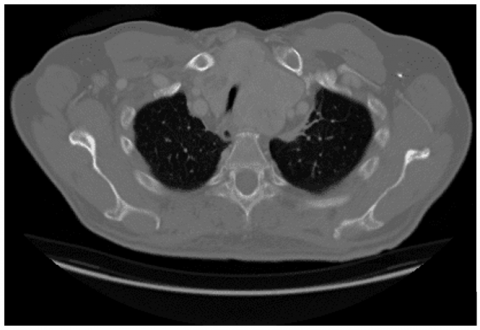

The first stage of the developed framework is the lung CT image acquisition from both healthy and cancer-affected persons as shown in Figure 2. The gathered images are labeled to train the classifier to recognize the patterns of lung cancer. The presented study used the publicly available Lung CT scan database from Kaggle site [27].

Figure 2. Dataset images of different classes: (a) Lung cancer; (b) Normal